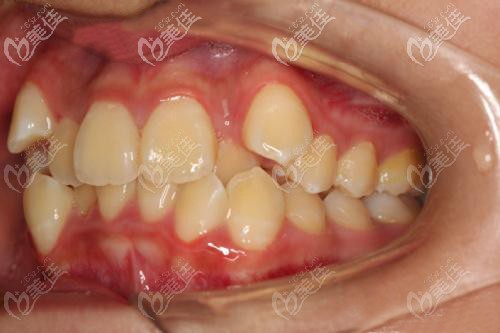

術(shù)前照片:

我本人是牙齒擁擠,一直想做矯正;所以,前兩天到就到我們漢口比較有名的連鎖牙科——牙達(dá)人口腔看看究竟做牙齒矯正怎么樣!下面是我偶遇到一位17歲小妹妹牙列擁擠,戴金屬自鎖矯正器14個(gè)月的真實(shí)案例,分享給大家。

為何17歲就要戴牙套矯正牙齒擁擠:

牙列擁擠還導(dǎo)致了牙齒聚結(jié)、重疊和扭曲,長得亂七八糟。不僅僅是難看,而且刷牙和使用牙線都清理不干凈牙縫的殘留物;時(shí)間一長,還出現(xiàn)了蛀牙~